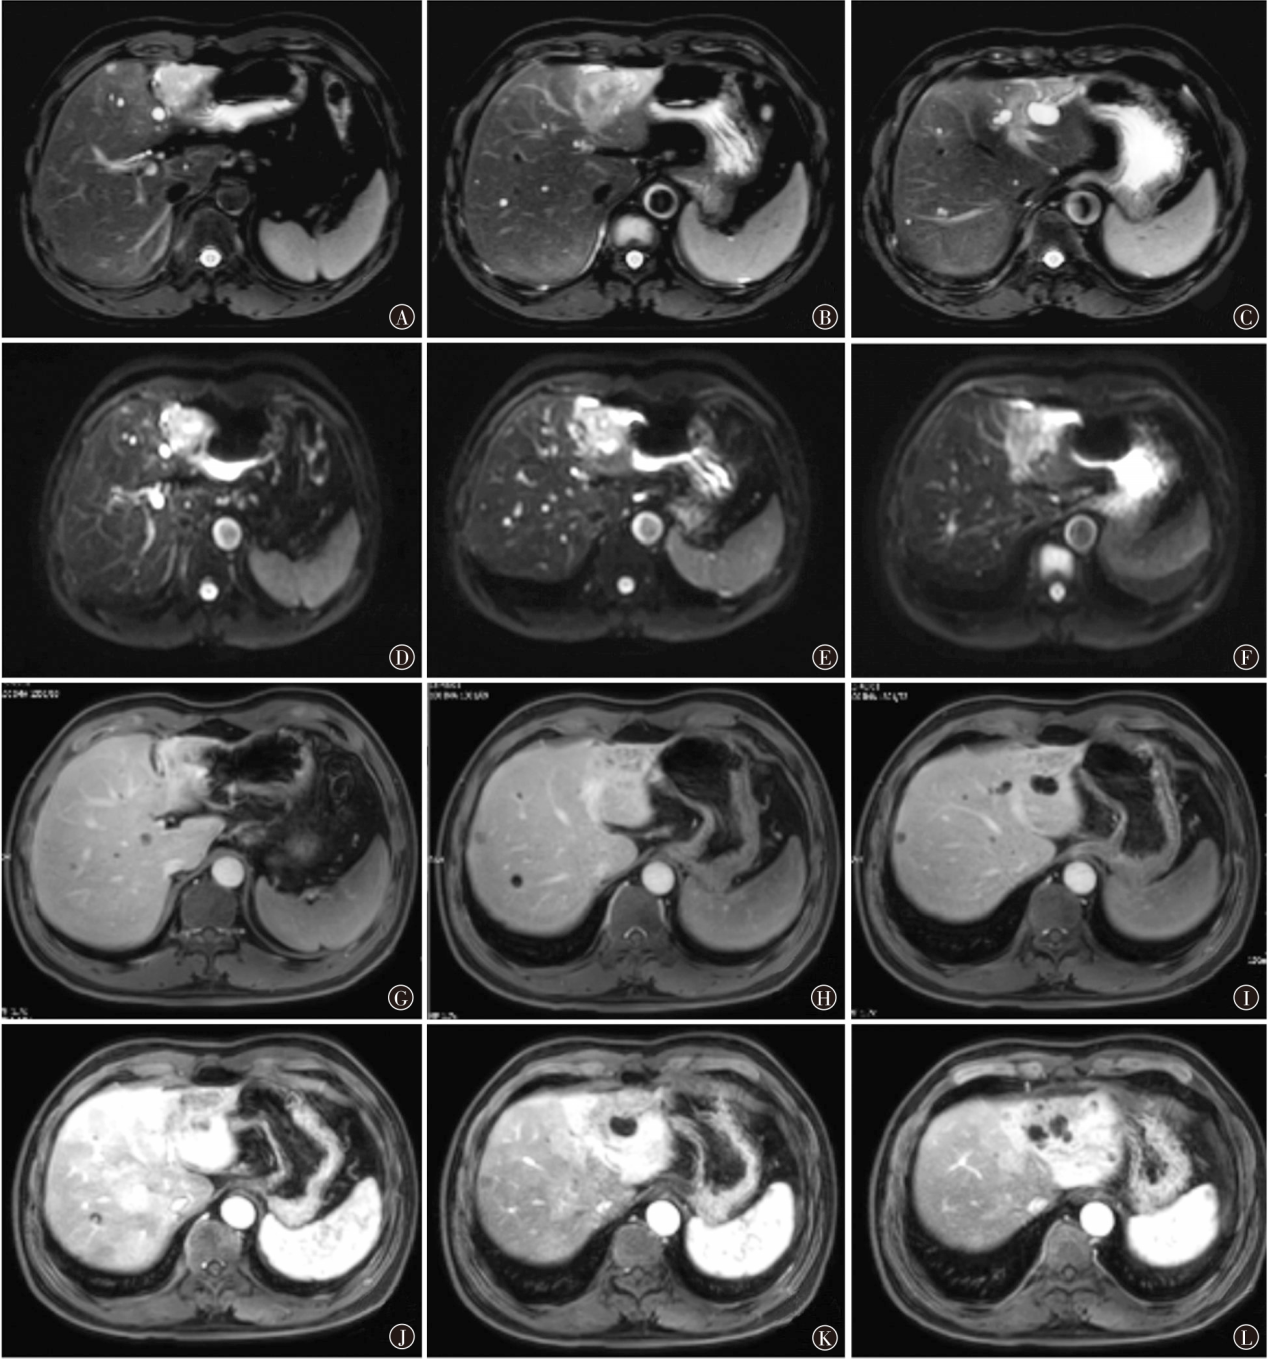

肝内胆管癌(ICC)是消化系统常见肿瘤,起源于肝内胆管上皮细胞,其发病隐匿,早期诊断困难,恶性程度高,预后极差。索凡替尼为我国自主研发的血管内皮生长因子受体酪氨酸激酶抑制剂,此前主要用于非胰腺神经内分泌瘤患者的治疗,最近研究发现其在胆道肿瘤中疗效确切,现报道1例索凡替尼靶向联合卡培他滨+奥沙利铂治疗ICC术后患者,以期为ICC的临床治疗提供参考。